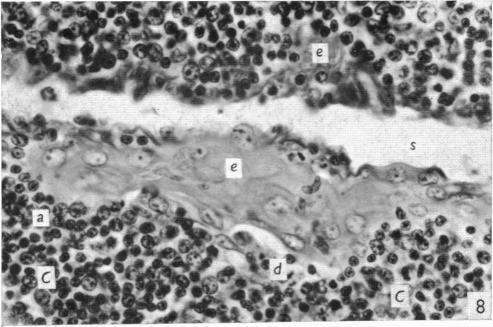

The effect of castration, oestrogens, testosterone and the oestrous cycle on the cortical epithelium of the thymus in male and female rats.

J Anat. 1968 Jun;103(Pt 1):113-33.